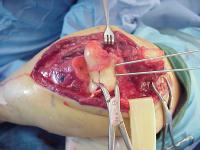

Open reduction via olecranon osteotomy.  The ulnar nerve is  retracted with a penrose drain. The articular surface was reconstructed, then secured to the shaft. After recovering the rotated anterior articular fragment, the anterior and posterior halves of the central articular component were secured with .062" pins. These pins were replaced one at a time with Herbert screws.

Later in the case, the small medial osteochondral fragment was secured with absorbable sutures (not shown).

In similar steps, the reconstructed central articular component was secured to the proximal humerus with pins. Once satisfactory reduction was obtained (not yet, as seen here...), the pins were replaced by more Herbert screws. This allowed fixation of the purely osteochondral segments without prominent harware.